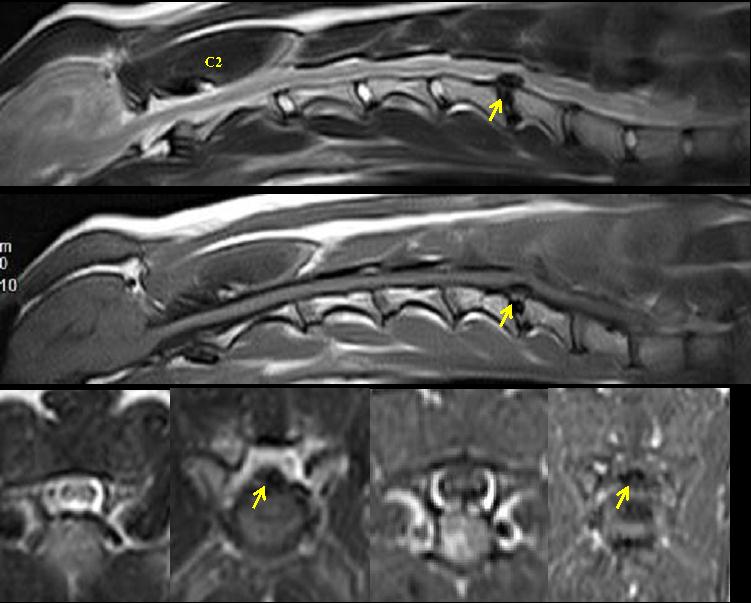

神经学病变定位:MRI检查,可见 C5-6 椎间盘矿化、脱出,椎管内占位明显,约为 50%,局部脊髓受压变形(见图1)。C1-C5脊髓神经损伤,瘫痪程度3/5。

图1 Vega的颈部MRI影像